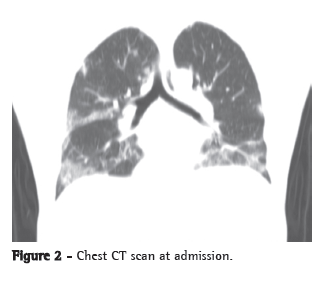

A chest X-ray showed worsening of the bilateral alveolar infiltrate, and a chest CT scan showed multifocal ground-glass infiltrate (Figures 1 and 2).

On chest CT scans, various patterns are possible. However, the ones most commonly reported are those showing lobular areas, typically bilateral, of ground-glass attenuation. Other possible patterns are the presence of focal areas of consolidation, centrilobular nodules and the tree-in-bud pattern.(9)